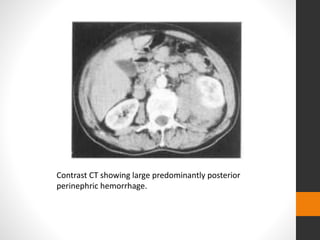

Contrast CT showing large predominantly posterior

perinephric hemorrhage.